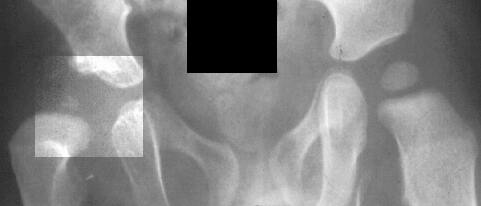

Physical exam showed the right hip to be dislocated. X-rays demonstrated

a dislocation of the right hip without the presence of an ossific nucleus

on the right side suggesting ischemic necrosis.

X-rays

and

arthrogram at two years of age show irregular ossification of the femoral

head and dysplastic acetabulum,

but the hip coverage was acceptable even in adduction.